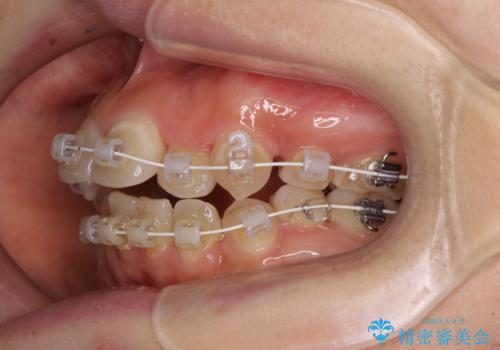

- 矯正装置

- 審美装置

- 前歯の著しいデコボコを気にして来院された患者様です。

上顎の左右側切歯(前から2番目)が裏側に隠れいてる状態で、咬み合わせや清掃性に大きな問題が認められました。

叢生が著しいため、左下以外の第一小臼歯3本を抜去し、目立たないワイヤー装置にて矯正治療を行うこととしました。

これほど顕著に裏側に隠れいてる歯ですと、仕上がったときに両隣の歯と軸に差が認められることが多いのですが、殆ど違和感のない歯並びを達成することができました。